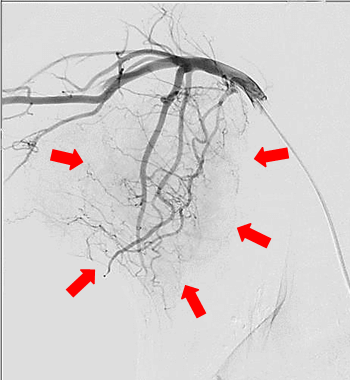

【実施症例】甲状腺癌に対する動注療法

ミニチュア・ダックスフンド、12歳、雌。

周囲組織に浸潤した甲状腺癌で外科的切除は困難であった。 大腿動脈からカテーテルを挿入し、腫瘍栄養血管である甲状腺動脈に抗がん剤と塞栓物質の選択的注入を行った。 実施後、腫瘍は縮小し症状の改善が得られた。

造影CT画像

実施前の血管造影(腫瘍内に血流が豊富に認められる)

実施前の血管造影

(腫瘍内に血流が

豊富に認められる)